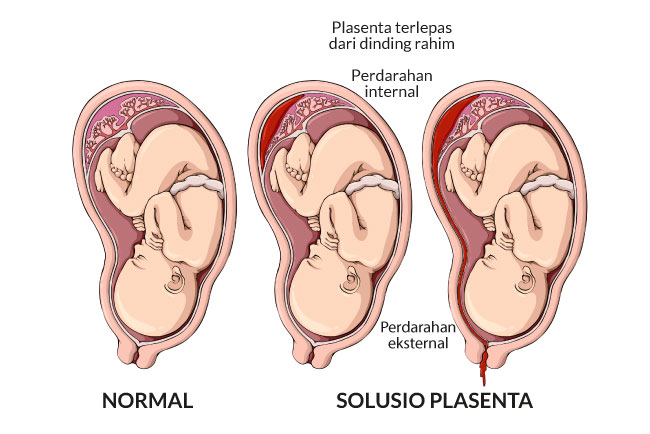

Duh, Plasenta Lepas Saat Hamil - Nakita

Duh, Plasenta Lepas Saat Hamil - Nakita

Solusio Plasenta - Gejala, penyebab dan mengobati - Alodokter

Solusio Plasenta - Gejala, penyebab dan mengobati - Alodokter

15 Perbedaan Plasenta Previa dan Solusio Plasenta | HonestDocs

15 Perbedaan Plasenta Previa dan Solusio Plasenta | HonestDocs